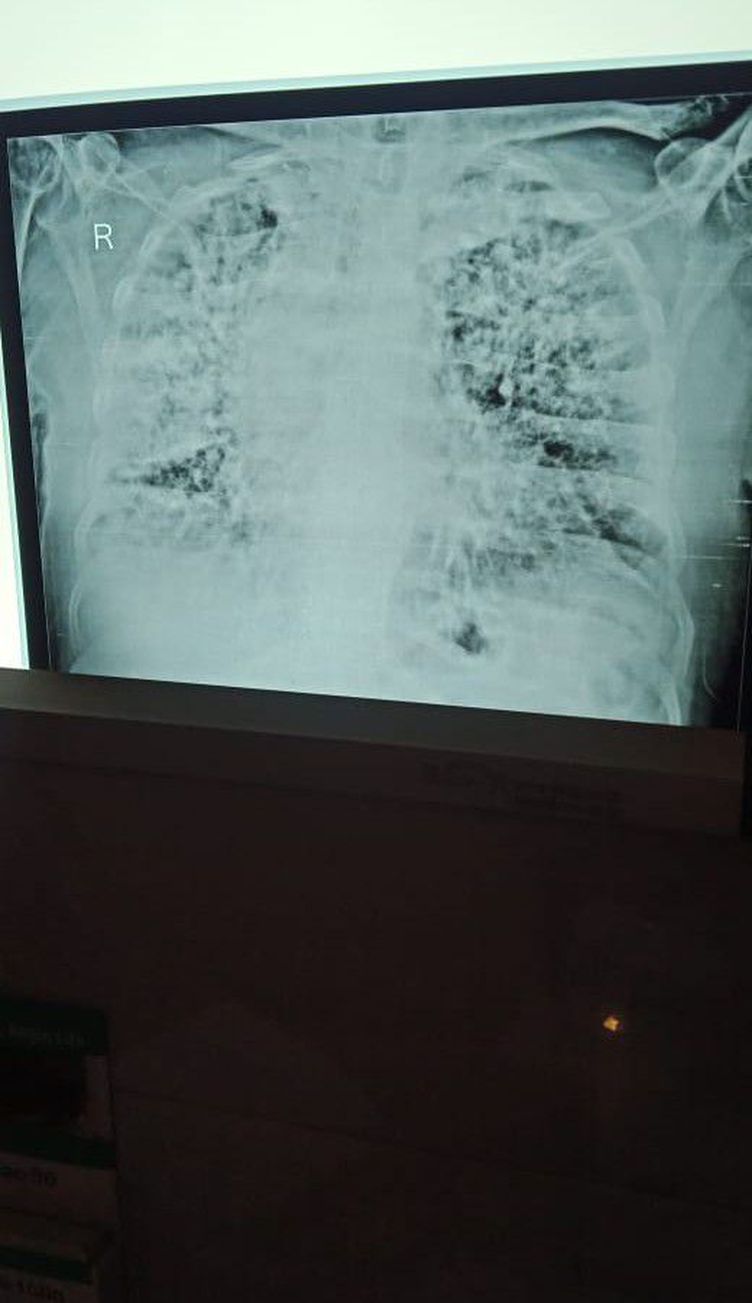

Diagnose fast

Radiology

Pulmonology

Chestxray

ARDS or pulmonary edema

looks like really bad lung fibrosis